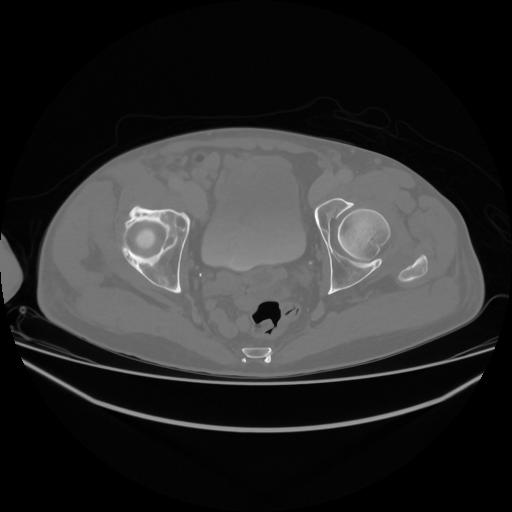

5 CUERPO,CE,Vol,1.0,CUERPO,,